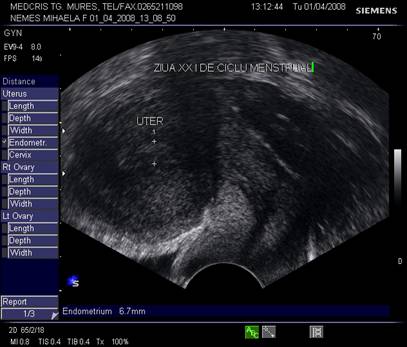

Fig. Nr. 360.Ovar sub vasele iliace , in ziua a XXI a de ciclu menstrual

Grosimea endometrului este de circa 1-2 mm la inceput de faza proliferativa, de cca 5 mm in ziua 10 -11, cu 1 zi preovulator cca 10 - 12 mm,apoi stagneaza, toate acestea la un ciclu menstrual de 28 zile.[2,6]